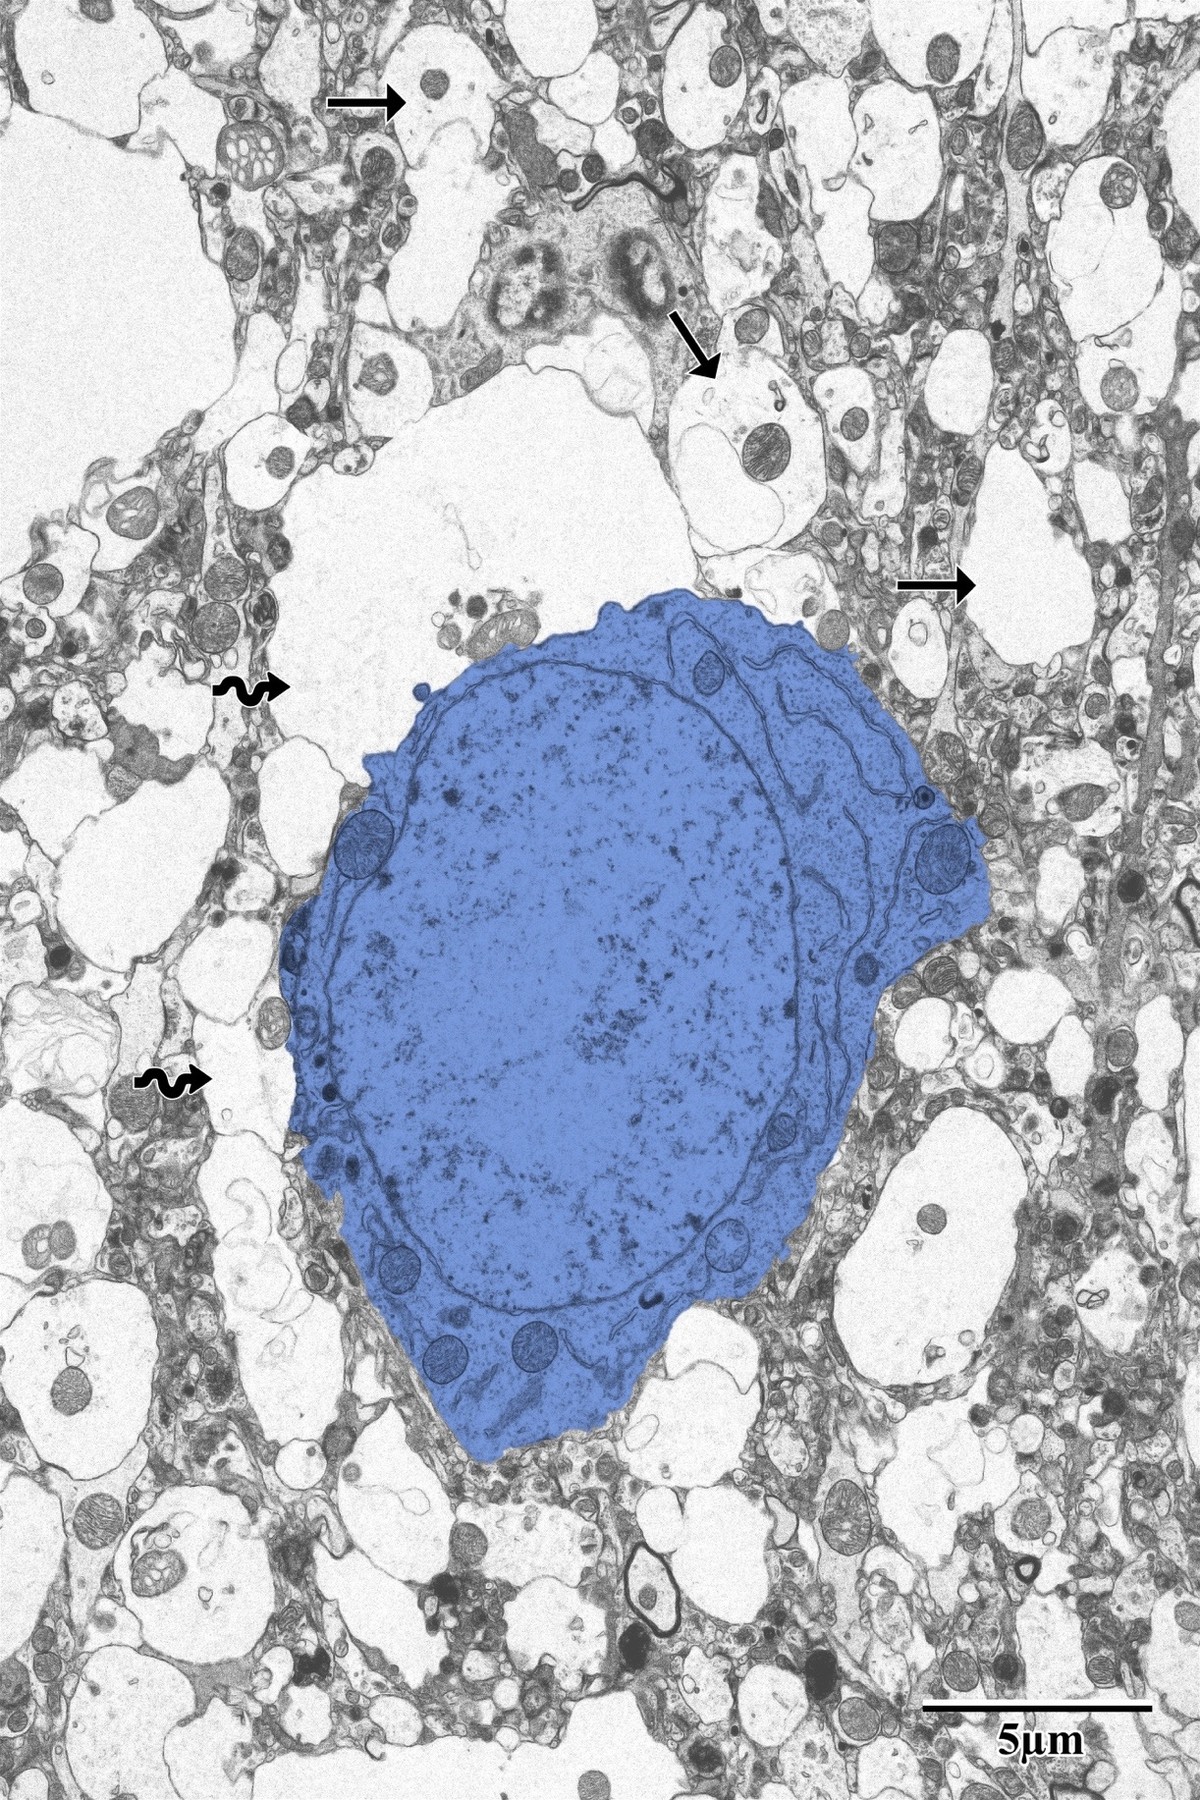

Control Pyramidal Neurons

In the contralateral (uninjured) hemisphere, pyramidal neurons display round, electron-lucent morphology with intact nuclear envelopes, prominent nucleoli, and well-organized cytoplasmic organelles. Astrocytes (wavy arrows) occupy relatively limited space in the surrounding neuropil.

Control pyramidal neurons with healthy round morphology in contralateral SSC

Pyramidal neurons (blue) within the contralateral SSC exhibiting round morphology with intact cellular processes (arrows) and healthy astrocytes (wavy arrows). From Bayati, BSc Honours Thesis 2018.